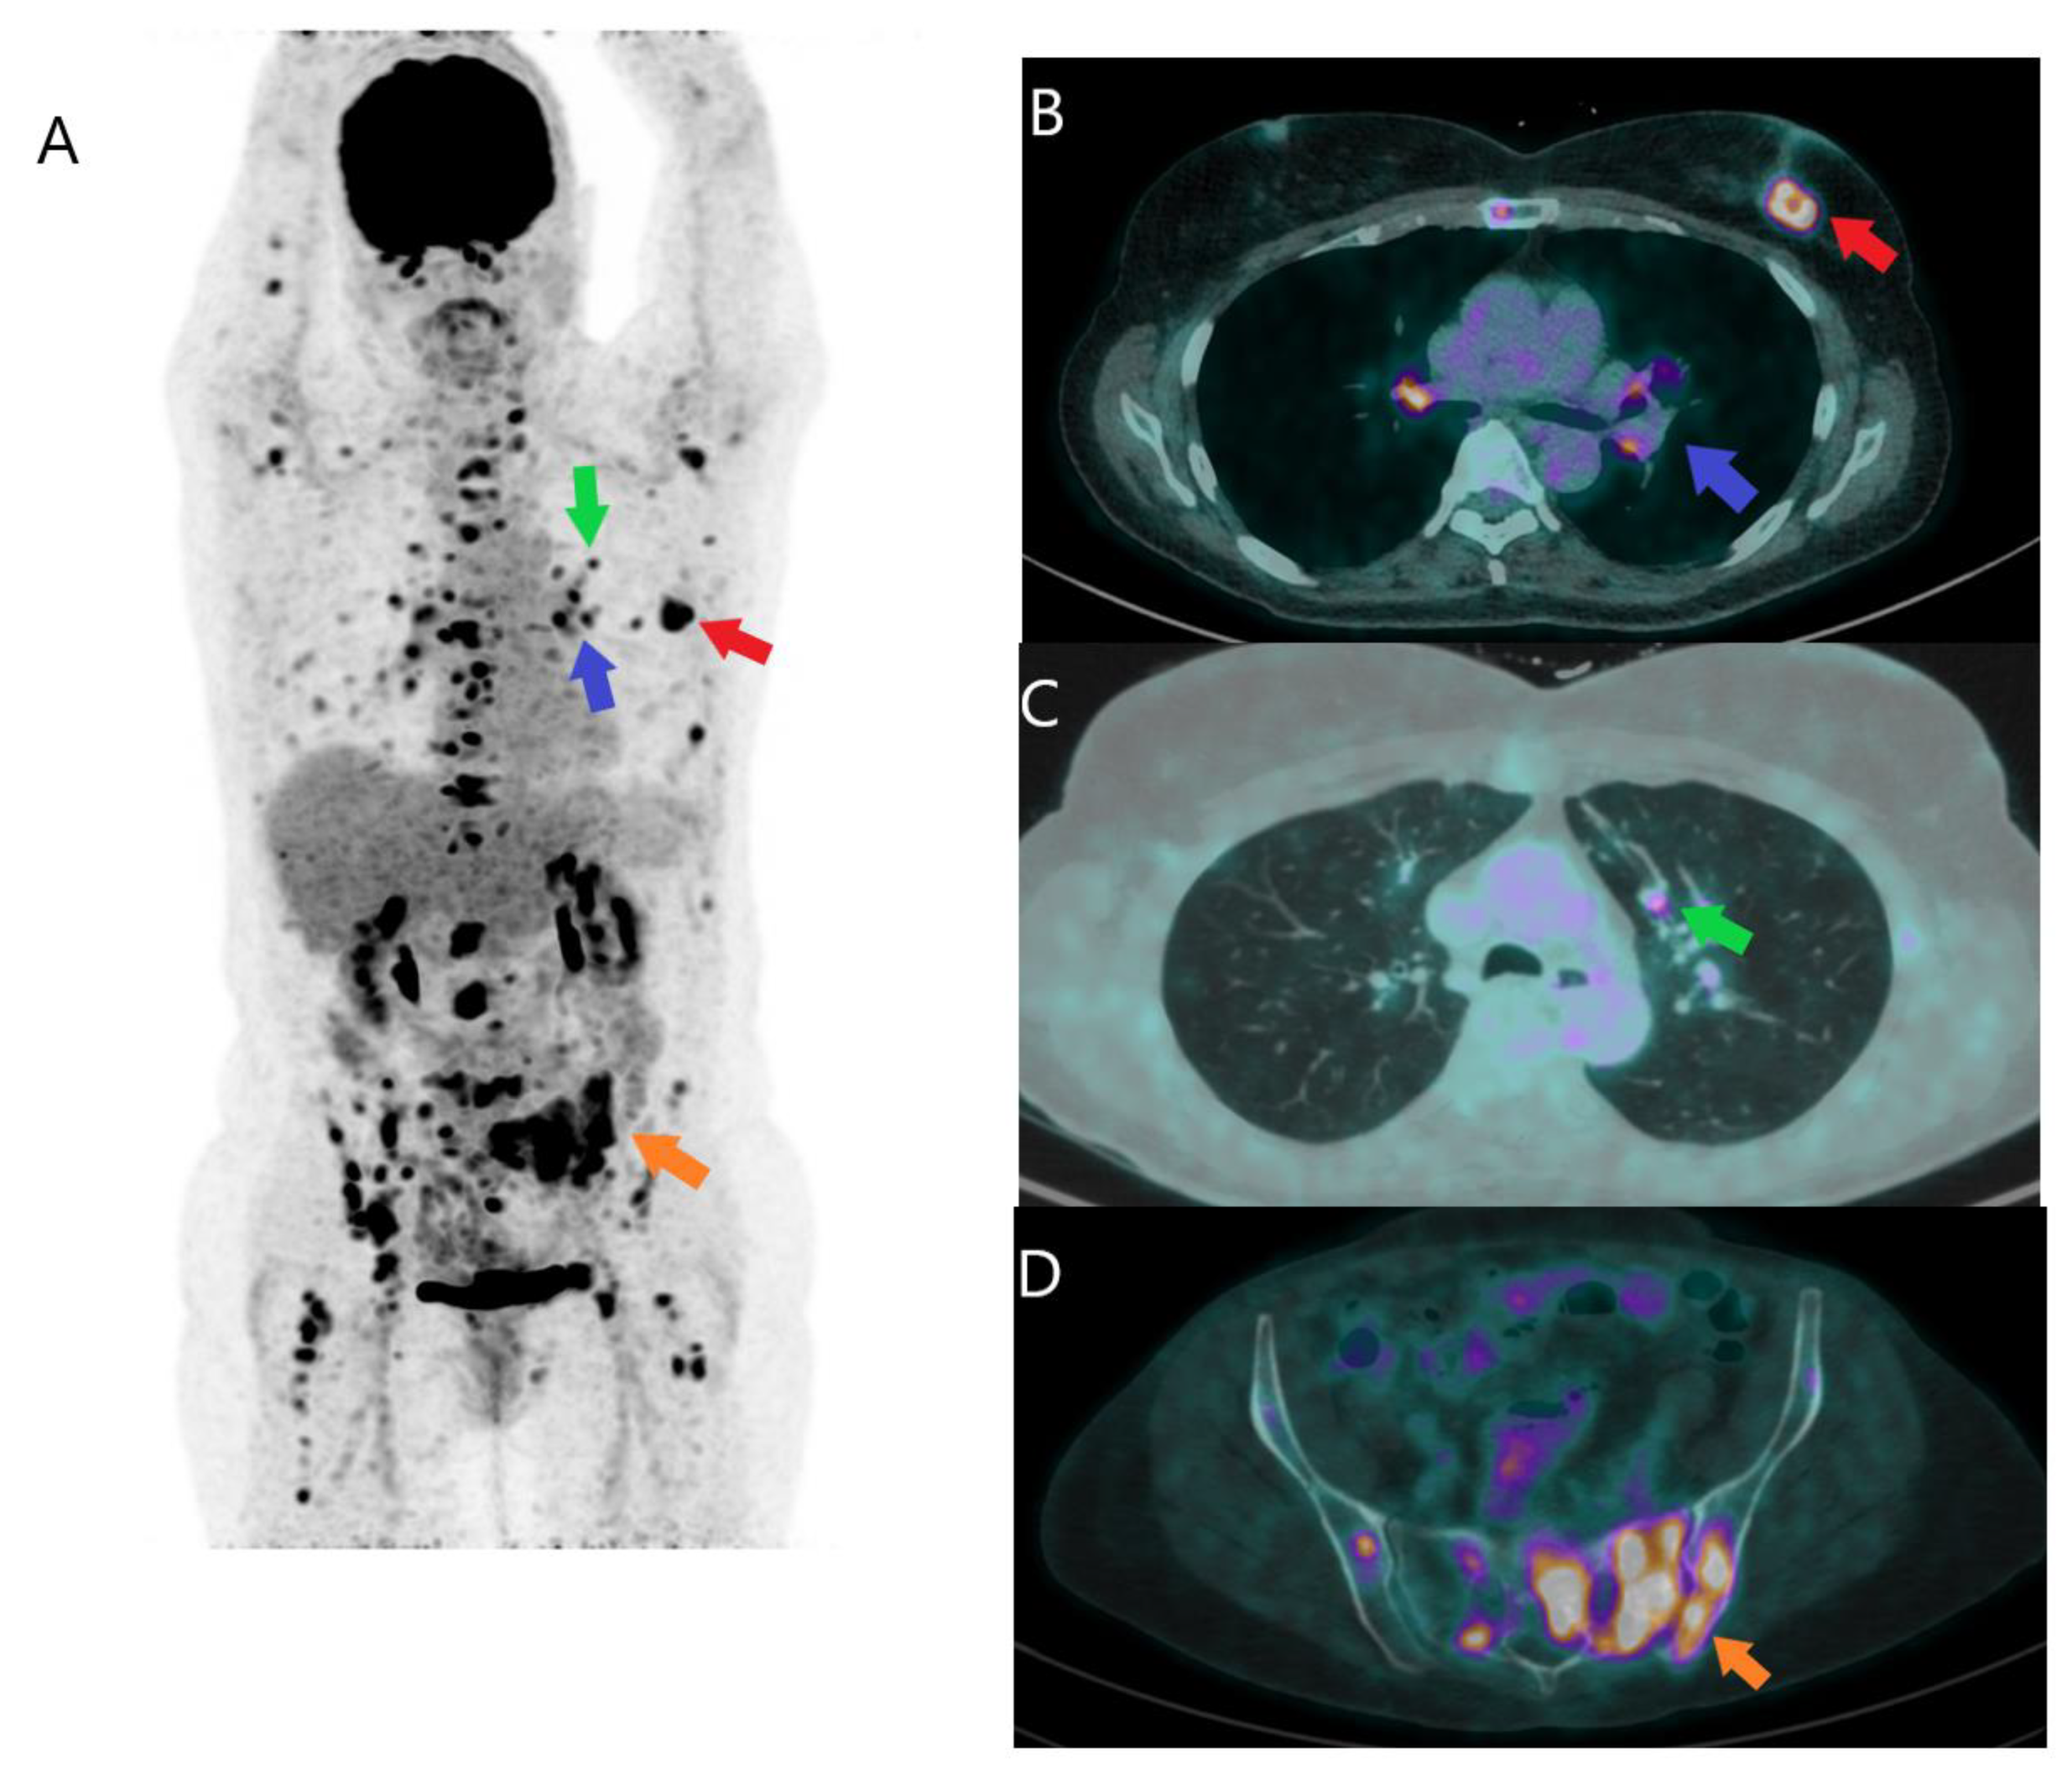

2.3.1. Metastatic Disease

2.3.2. Neoadjuvant Treatment Response for Primary Tumor